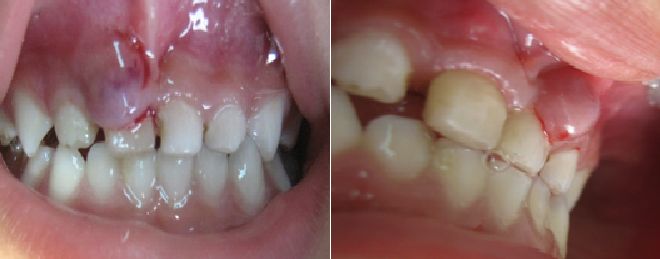

- TRAUMA DENTOALVEOLAR Y MAXILAR:

Cada vez son más frecuentes en la consulta particular e institucional, las lesiones de origen traumático en la dentición temporal y permanente joven.

Fracturas coronales, fracturas radiculares, luxaciones dentales, abrasiones y erosiones, avulsiones son entre otras situaciones de manejo urgente y que requieren el tratamiento oportuno por parte del especialista en Odontología Pediátrica que favorezca óptimos pronósticos y resultados adecuados.